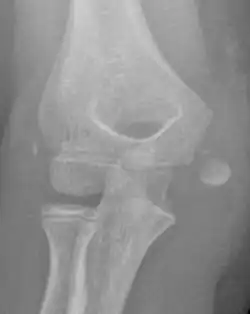

The diagnosis is confirmed with X-rays and occasionally with a CT scan.

In all injuries to the medial epicondyle, radiographs (x-rays) are imperative. Computed tomography scans are occasionally useful in evaluating the degree of fracture displacement or the involvement of the joint surface.

Studies generally use the x-ray appearance of the arm to determine how displaced a fracture is. The definition of ‘displaced fractures' are variable, with anything from 2mm to more than 15mm;[4] however x-rays on which this assessment is made are known to be hugely misleading with fractures showing little displacement having >10mm displacement using CT scans.[5][6] The practical approach is therefore to assume that any fracture that has any degree of displacement on x-rays is ‘displaced’.